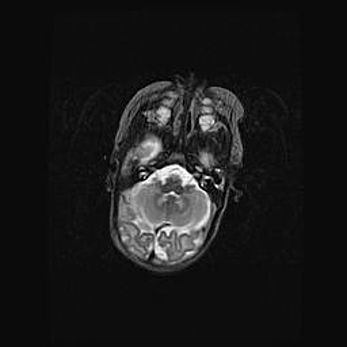

Мальформация Денди-Уокера. Киста задней черепной ямки.

Агенезия мозолистого тела.

Возраст: 2,5 месяца

Вес: 2420 г

Пол: женский

Окружность головы: 37 см

Срок гестации: 32 недели

Мальформация Денди—Уокера — редкий вид патологии ЦНС, представляющий собой врожденный порок развития каудального отдела ствола и червя мозжечка, ведущий к неполному раскрытию срединной (Мажанди) и латеральных (Лушка) апертур IV желудочка мозга. Для этогно синдрома характерна триада симптомов: гипотрофия червя мозжечка и/или полушарий мозжечка, кисты задней черепной ямки, гидроцефалия различной степени. В 70% случаев порок сочетается и с другими аномалиями головного мозга, в частности с агенезией мозолистого тела.